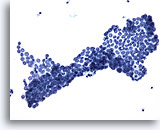

Figure 13

Peritoneal wash: Benign. 20X

Figure 13

Peritoneal wash:

Benign.

20X

For peritoneal washings the surgeon performs an irrigation or barbitage to collect cells for analysis. Pelvic mesothelial cells may be shed in broad and flat sheets. Sometimes the sheets fold so that overlapping of cells is evident. The benign nature of these mesothelial cells is obvious by their uniform arrangement and appearance.